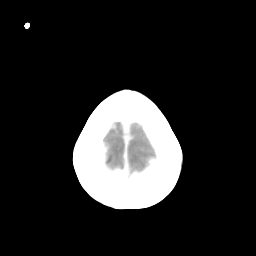

Metastatic bronchogenic carcinoma: Roentgen-ray CT -- Slice #21

[Home][Help][Clinical] Slice 21